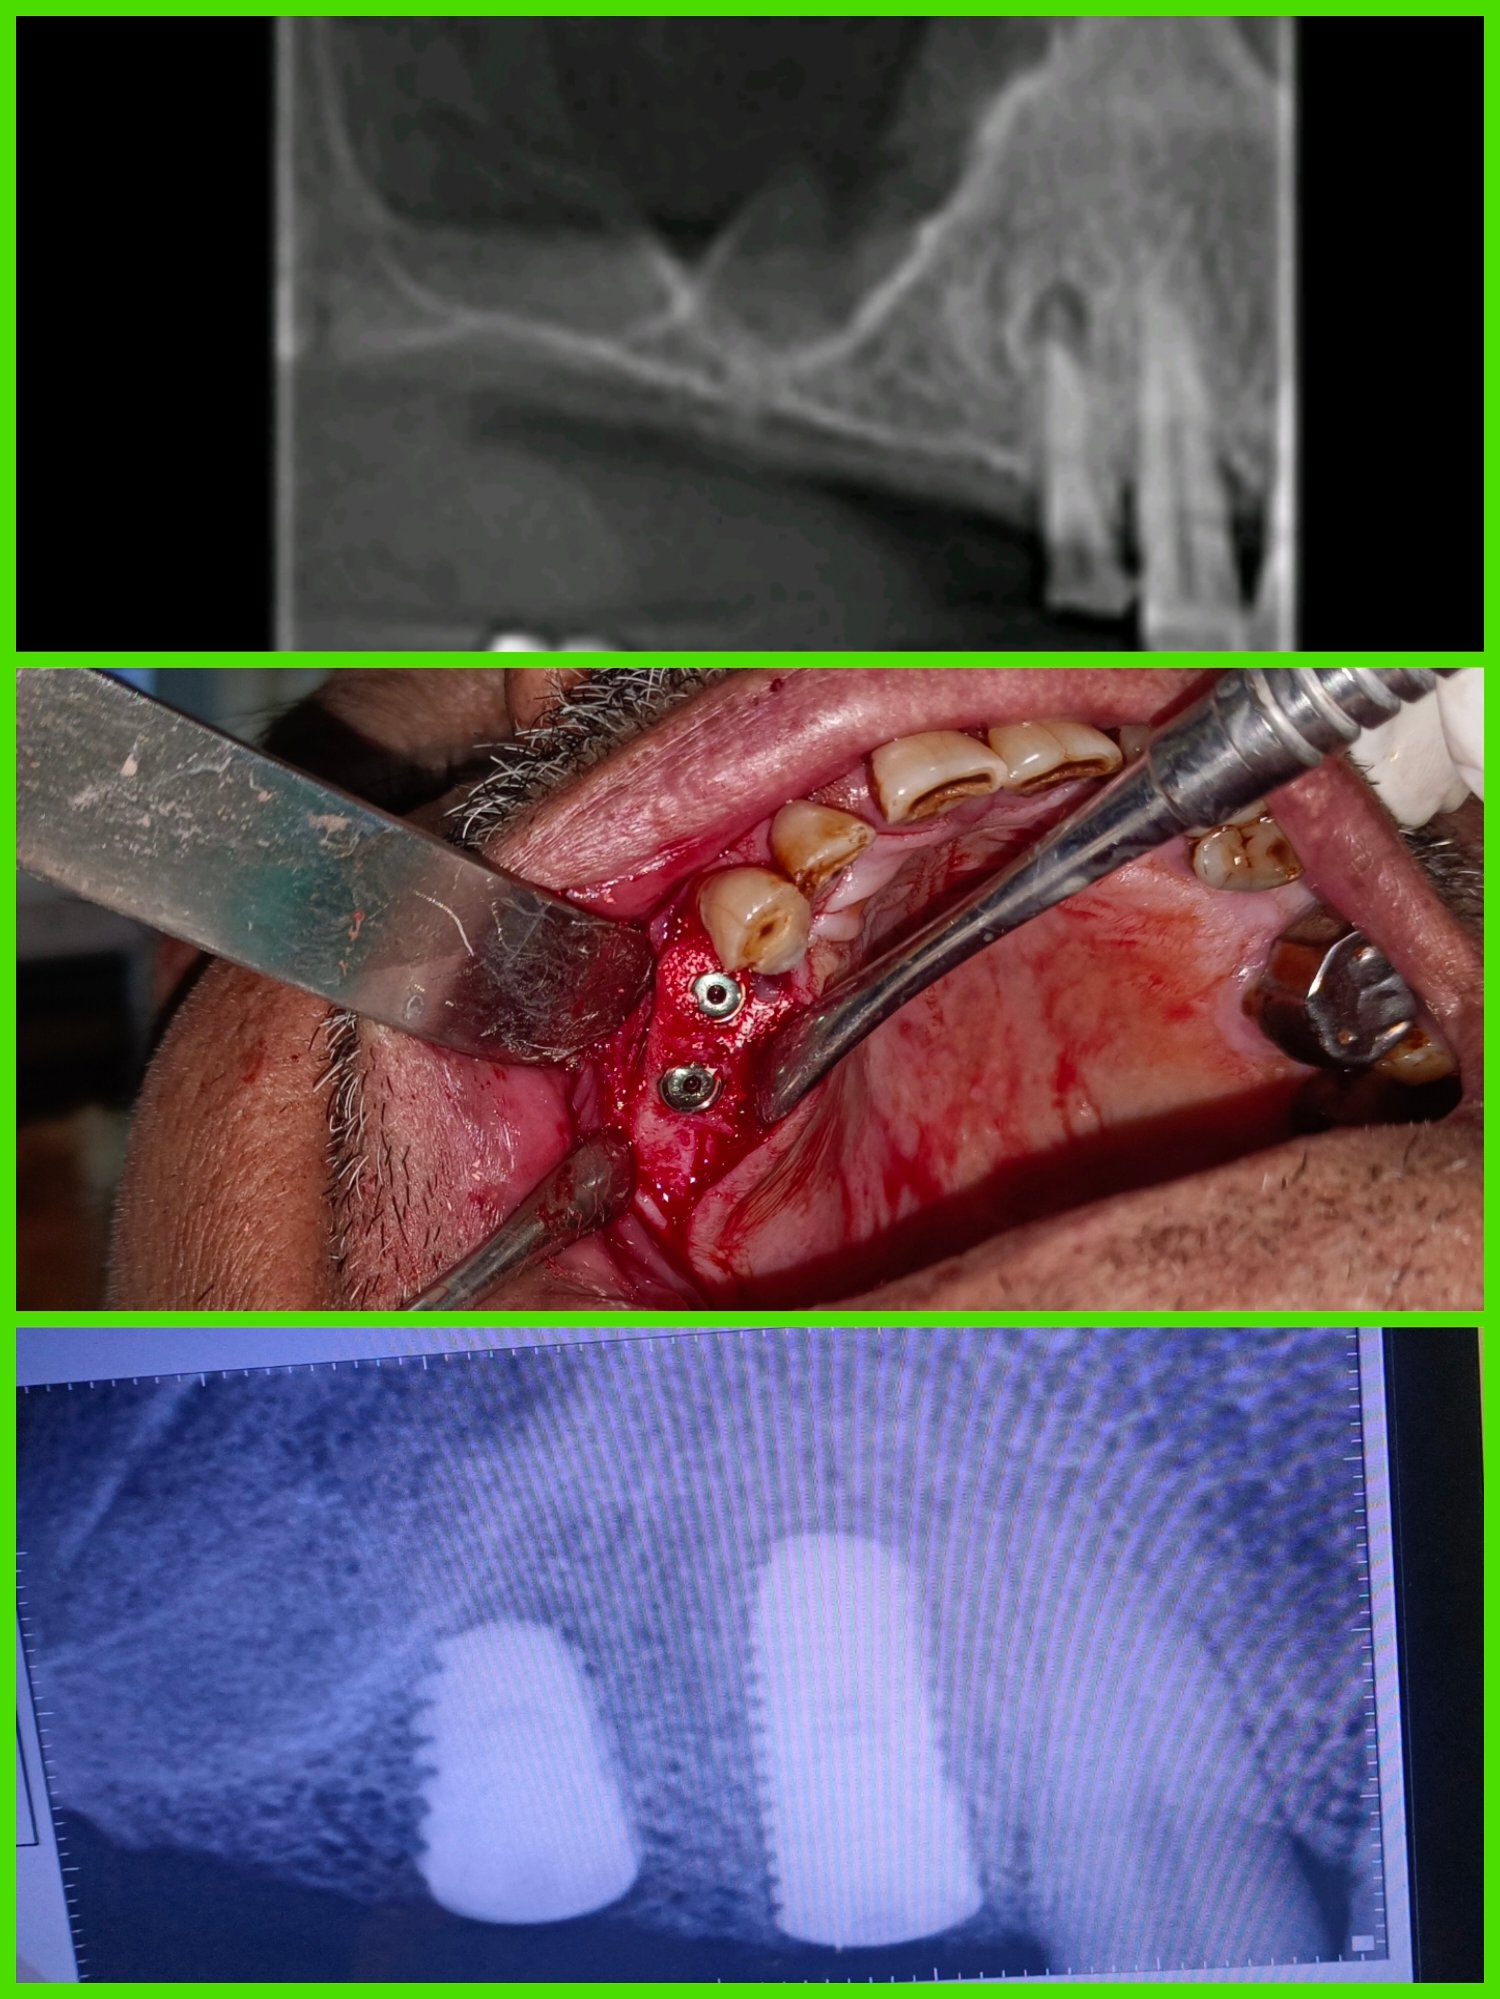

ЁЯПе рдзрд╛рд░рд╛рд╢рд┐рд╡ рдЬрд┐рд▓реНрд╣реНрдпрд╛рддреАрд▓ рдкреНрд░рд╕рд┐рджреНрдз рдбреЗрдВрдЯрд▓ рд╣реЙрд╕реНрдкрд┐рдЯрд▓ & рдлреЗрд╢рд┐рдпрд▓ рдЯреНрд░реЙрдорд╛ рдХреЗрдЕрд░ рд╡ рдЗрдореНрдкреНрд▓рд╛рдВрдЯ рд╕реЗрдВрдЯрд░ ЁЯПе ЁЯПердЕрддреНрдпрд╛рдзреБрдирд┐рдХ рдбрд┐рдЬрд┐рдЯрд▓ рдПрдХреНрд╕-рд░реЗ ЁЯПердЗрдВрдЯреНрд░рд╛ рдУрд░рд▓ рдХреЕрдореЗрд░рд╛ рджреНрд╡рд╛рд░реЗ рддрдкрд╛рд╕рдгреА ЁЯж╖рдЕрд▓реНрдЯреНрд░рд╛рд╕реЛрдирд┐рдХ рдорд╢реАрдирджреНрд╡рд╛рд░реЗ рджрд╛рдд рд╕рд╛рдл рдХрд░рдгреЗ ЁЯж╖рдХреГрддреНрд░рд┐рдо рджрдВрддрд░реЛрдкрдг ЁЯж╖рдЕрдХреНрдХрд▓рджрд╛рдбреЗ рд╡рд░реАрд▓ рд╢рд╕реНрддреНрд░рдХреНрд░рд┐рдпрд╛ ЁЯж╖рдЬрдмрдбреНрдпрд╛рдВрдЪреЗ рдлреНрд░реЕрдХреНрдЪрд░ рд╡рд░реАрд▓ рд╢рд╕реНрддреНрд░рдХреНрд░рд┐рдпрд╛ ЁЯзмрдЕрддреНрдпрд╛рдзреБрдирд┐рдХ рдкрджреНрдзрддреАрдиреЗ рджрд╛рддрд╛рдВрдЪреНрдпрд╛ рдирд╕рд╛ рд╡рд░реАрд▓ рдЙрдкрдЪрд╛рд░ ЁЯзмрддреЛрдВрдбрд╛рддреАрд▓ рдореМрдЦрд┐рдХ рд╢рд╕реНрддреНрд░рдХреНрд░рд┐рдпрд╛ ЁЯзмрд╕рдВрдкреВрд░реНрдг рдХрд┐рдВрд╡рд╛ рдЕрдВрд╢рддрдГ рдХрд╡рд│реА рдмрд╕рд╡рдгреЗ ЁЯзмрд╡реЗрдбреЗрд╡рд╛рдХрдбреЗ рджрд╛рдд рд╕рд░рд│ рдХрд░рдгреЗ

ЁЯПе рдлреЗрд╢рд┐рдпрд▓ рдЯреНрд░реЙрдорд╛ рдХреЗрдЕрд░ рд╡ рдЗрдореНрдкреНрд▓реЗрдВрдЯ рд╕реЗрдВрдЯрд░

ЁЯПе рд╕реНрдХреНрд░реВ рдЪреНрдпрд╛ рд╕рд╛рд╣реНрдпрд╛рдиреЗ рдлрд┐рдХреНрд╕ рджрд╛рдд рдмрд╕рд╡рдгреЗ